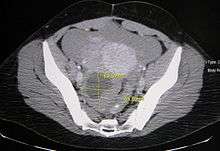

| A simple ovarian cyst of most likely follicular origin | |

Ovarian cysts are usually diagnosed by either ultrasound, CT scan or MRI, and correlated with clinical presentation and endocrinologic tests as appropriate.